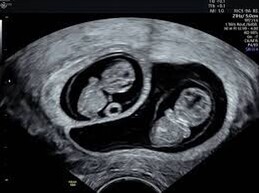

Our vision is to ensure that every family with multiples (twins, triplets, or more) feels supported and able to follow this ever-changing parenting journey with confidence.

Multiples Canterbury is a voluntary non-profit organisation run by parents of multiples of all ages - newborn babies through to teenagers - to advise, encourage and inform parents of multiples, parents expecting multiples, and anyone else who is the main caregiver of multiples.